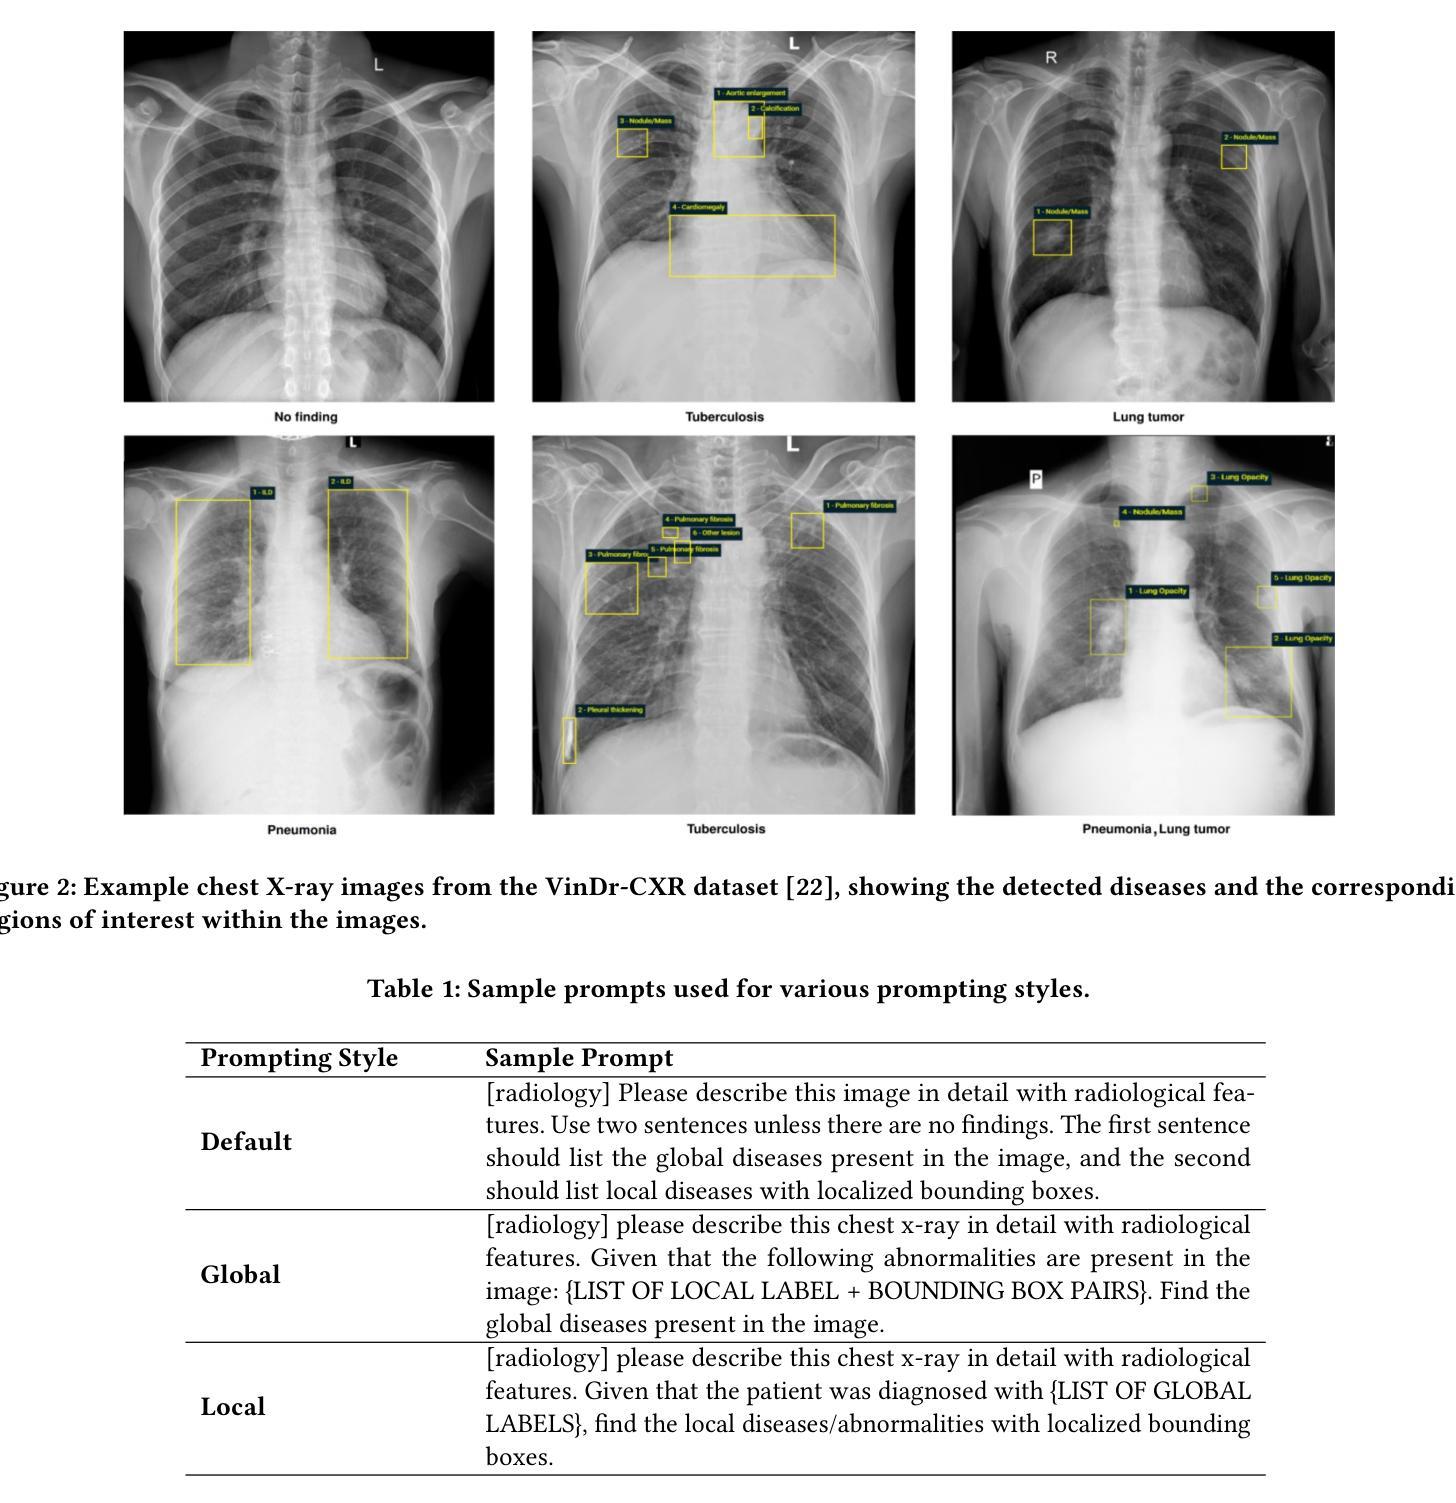

ChestGPT: Integrating Large Language Models and Vision Transformers for Disease Detection and Localization in Chest X-Rays

Authors:Shehroz S. Khan, Petar Przulj, Ahmed Ashraf, Ali Abedi

The global demand for radiologists is increasing rapidly due to a growing reliance on medical imaging services, while the supply of radiologists is not keeping pace. Advances in computer vision and image processing technologies present significant potential to address this gap by enhancing radiologists’ capabilities and improving diagnostic accuracy. Large language models (LLMs), particularly generative pre-trained transformers (GPTs), have become the primary approach for understanding and generating textual data. In parallel, vision transformers (ViTs) have proven effective at converting visual data into a format that LLMs can process efficiently. In this paper, we present ChestGPT, a deep-learning framework that integrates the EVA ViT with the Llama 2 LLM to classify diseases and localize regions of interest in chest X-ray images. The ViT converts X-ray images into tokens, which are then fed, together with engineered prompts, into the LLM, enabling joint classification and localization of diseases. This approach incorporates transfer learning techniques to enhance both explainability and performance. The proposed method achieved strong global disease classification performance on the VinDr-CXR dataset, with an F1 score of 0.76, and successfully localized pathologies by generating bounding boxes around the regions of interest. We also outline several task-specific prompts, in addition to general-purpose prompts, for scenarios radiologists might encounter. Overall, this framework offers an assistive tool that can lighten radiologists’ workload by providing preliminary findings and regions of interest to facilitate their diagnostic process.

Summary

本文介绍了全球对放射科医生的需求迅速增长,而放射科医生的供应却跟不上这一需求。计算机视觉和图像处理技术的进步为解决这一差距提供了巨大潜力,通过增强放射科医生的能力和提高诊断准确性来实现。本文提出了一种名为ChestGPT的深度学习框架,它结合了EVA Vision Transformer(ViT)和Llama 2大型语言模型(LLM),用于对胸部X射线图像进行疾病分类和感兴趣区域定位。该框架使用ViT将X射线图像转换为令牌,然后与工程提示一起输入LLM,实现疾病的联合分类和定位。该方法采用迁移学习技术,提高了可解释性和性能。在VinDr-CXR数据集上,该方法实现了强大的全球疾病分类性能,F1分数为0.76,并成功定位了病理区域,生成了围绕感兴趣区域的边界框。总体而言,该框架为放射科医生提供了一种辅助工具,可以通过提供初步发现和感兴趣区域来减轻他们的工作量,从而有助于诊断过程。